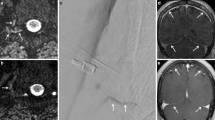

What do we know about CSF resorption? Three important pathways of CSF absorption may be distinguished: first, the widely recognized route via cranial arachnoid granulations [9]; second, via spinal arachnoid granulations (SAG), which are mostly adjacent to a radicular vein, and mainly located on the dorsal nerve root (Fig. 4a; [17, 18]); third, and less well known, along cranial and spinal nerve sheaths into the lymphatic system, which then drain into lymph nodes [19]. Direct lymphatic drainage into deep cervical and prevertebral lymph nodes via epidural lymphatics, which originate from the spinal meninges and are well developed in the upper spine, has been reported by Miura et al. [10]. In humans, spinal CSF absorption accounts for approximately 20% of the total outflow [20].

Illustration of the spine depicting the epidural venous plexus (blue). Spinal arachnoid granulations (SAG) are illustrated with the outflow (arrow) of cerebrospinal fluid (CSF) into the adjacent radicular vein. a Illustration of the normal CSF resorption along spinal arachnoid granulations. b Illustration of a spinal CSF leak. CSF leaks from the intrathecal to the epidural compartment via a dural breach (asterisk) where it is resorbed and finally excreted into the renal collecting system. In addition, resorption through SAGs is demonstrated. c Illustration of a spinal meningeal cyst with increased CSF resorption into the adjacent epidural vein via SAGs. This might be the underlying pathomechanism of CSF hyperresorption in SIH. Depending on the amount of contrast agent outflow through the SAG the finding may remain occult on imaging; or may be demonstrated as a CSF venous fistula (CSFVF) in a case of high flow. d Illustration of a CSFVF which has formed as a de novo abnormal connection

Besides the resorption via SAGs, contrast agent that has leaked into the epidural space through a dural breach might additionally be resorbed from this compartment and finally excreted into the renal collecting system (Fig. 4b). In SLEC(+) patients, diffuse leakage of contrast agent beyond the epidural space into paravertebral tissue, indicating a high-flow leak, was associated with a significantly higher renal pelvis density in our study (p < 0.001). This finding supports the assumption of an additional, and important pathway of CSF resorption from the epidural space. Our results are in line with a recent study by Behbahani et al. reporting on early renal opacification in patients with and without a dural tear [21]. With a smaller study population, and also including cases without SIH according to the ICHD‑3 criteria, the group reported an increased renal pelvis density in patients with CSF leak but not in patients without.

On the other hand, in SLEC(−) patients without proof of a CSF leak or a CSFVF, the underlying pathomechanism leading to increased renal pelvis opacification on PMCT remains unclear. Whether these patients should be considered false negatives for a dural CSF leak, or a CSFVF, or whether other forms of CSF loss may be responsible for this finding remains undetermined. As elucidated above, intrathecally injected contrast agent is absorbed through SAG and spinal nerve sheaths and has been reported to commence almost immediately after lumbar injection [22]; however, these pathways of CSF resorption are difficult to directly visualize on imaging and may be occult for the neuroimager. Thus, increased renal pelvis opacification on PMCT in SLEC(−) patients may be considered an indicator for increased spinal CSF resorption via SAG and spinal nerve sheaths, leading to functional CSF hypotension (Fig. 4c).

A tendency toward higher renal pelvis opacification on PMCT in SLEC(+) compared to SLEC(−) patients was demonstrated, indicating a potentially increased resorption in the former group when adding the resorption from the intrathecal and epidural spaces.

A hyperdense paraspinal vein sign was present in only 2 patients in our population, both with a coexisting spinal CSF leak. None of the SLEC(−) patients had a hyperdense paraspinal vein. In several studies the detection rate for CSFVF varied substantially depending on the imaging modality used and the time from contrast agent injection to PMCT [23,24,25]. Recently, Schievink et al. reported a high yield for detection of CSFVF on digital subtraction myelography in lateral decubitus position [26]. The explanation for the low detection rate in our population may be partly that this technique was not used in our study and patients without epidural CSF collection had conventional myelography in the prone position. Furthermore, in our experience, differentiating a true CSFVF from diffuse epidural contrast agent spillage may be challenging on PMCT. Whether CSFVF truly represents an epidural vein directly connected to the intrathecal space remains controversial, and the underlying mechanism leading to fistula formation is not well understood (Fig. 4d). Alternatively, CSFVF could represent a physiological increase in CSF drainage via SAG into a paraspinal vein (Fig. 4c); however, to our knowledge, there is no direct evidence that confirms this hypothesis.

Kranz et al. postulated that a focal rupture or failure of the SAG may be responsible for unregulated CSF resorption into an adjacent radicular vein, which could represent a CSFVF [27]. Support for their hypothesis came from an association of a CSFVF with a spinal meningeal diverticulum, which was present in 82% of their patients [23].